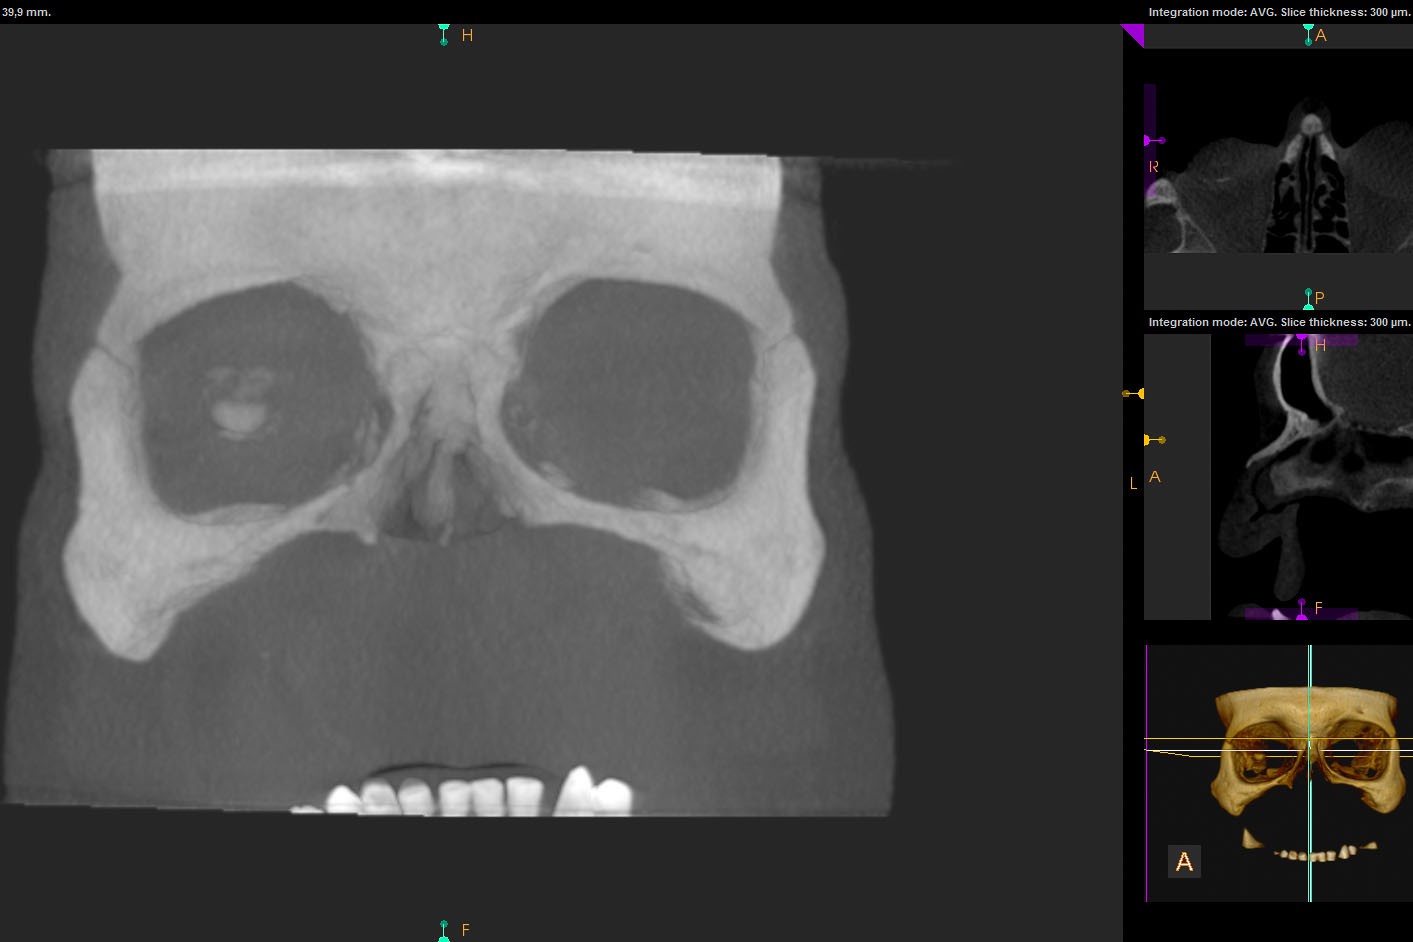

Chory po resekcji tkanek/narządów twarzoczaszki wymaga wnikliwej diagnostyki obrazującej zakres ubytku oraz stan podłoża kostnego. Wykonuje się zdjęcia radiologiczne RTG pantomograficzne szczęk OPG, konwencjonalną tomografię komputerową CT, stożkową tomografię komputerową CBCT, ukazującą trójwymiarowy obraz twarzoczaszki, oraz w razie potrzeby rezonans magnetyczny NMR. Możliwy jest również druk modeli 3D w skali 1:1 dowolnej części twarzoczaszki.

Diagnostyka ma za zadanie wykluczenie wznowy wyciętego nowotworu oraz pomoc w ocenie tkanki kostnej w okolicy ubytku. Ocena kości pozwala na zaplanowanie zabiegu wszczepienia implantów jako przyszłego fundamentu niezbędnego dla mocowania protez poresekcyjnych lub epitez twarzy.

Zastosowanie współczesnych technik obrazowania trójwymiarowego umożliwia precyzyjne zaplanowanie pozycji implantów czaszkowych, tak by ektoprotezę stabilnie osadzić na podłożu.